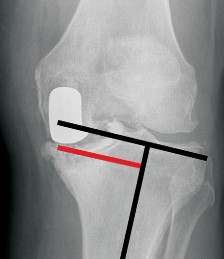

P ITFALLS Correct rotational positioning of the femoral and tibial components is a prerequisite for a success…

DEFINITION Total knee arthroplasty (TKA) is a successful surgical procedure that provides excellent and durab…

P ITFALLS Results of each type of alignment are technique dependent, and familiarity with each will reduce co…